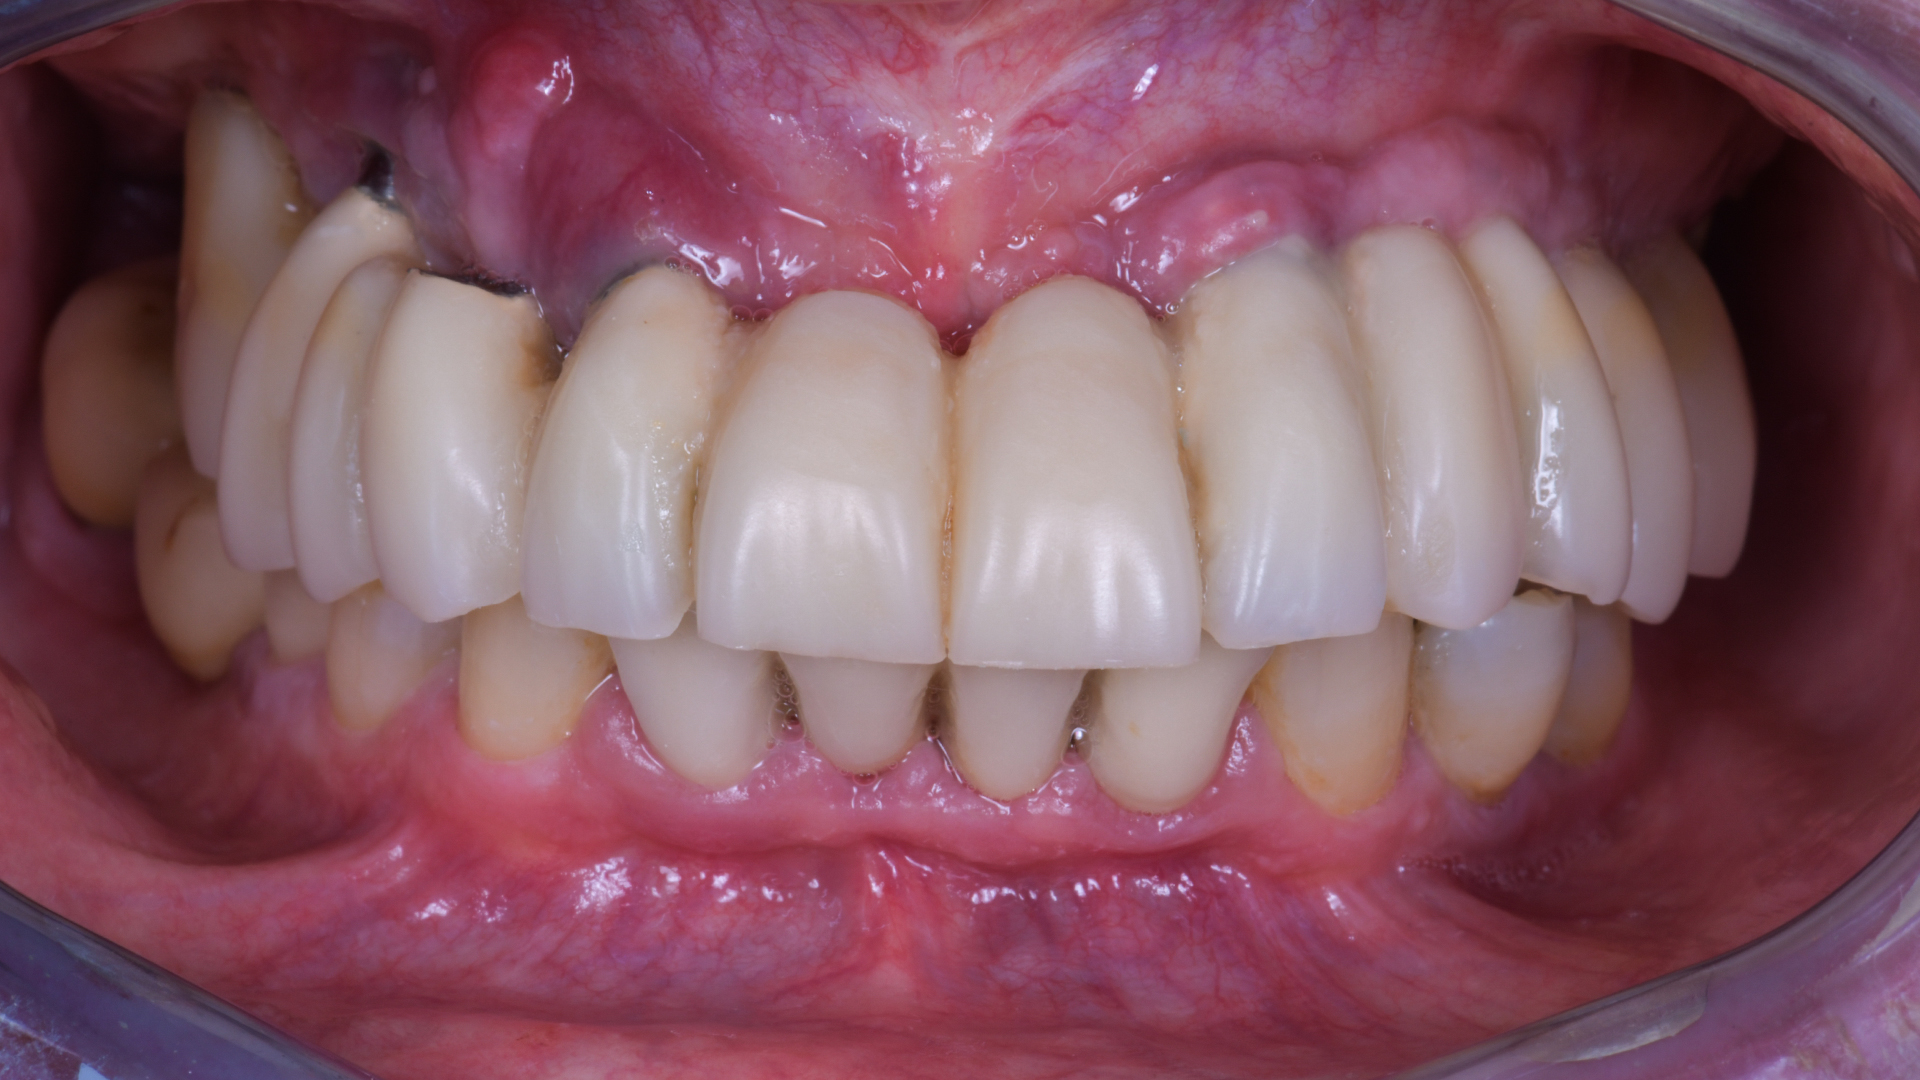

La situazione protesica precedente è questa e ti prometto che a breve pubblicherò anche la soluzione protesica del caso.